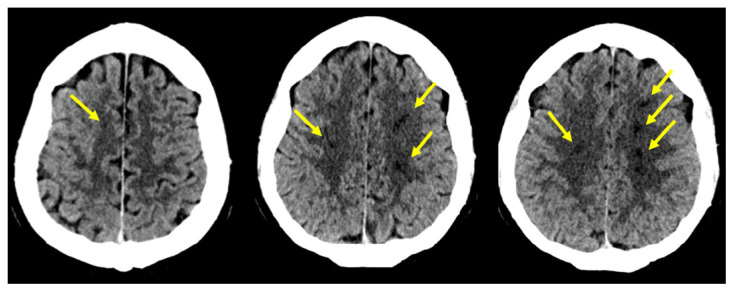

Acute Border Zone Infarcts in Hypereosinophilic Syndrome.